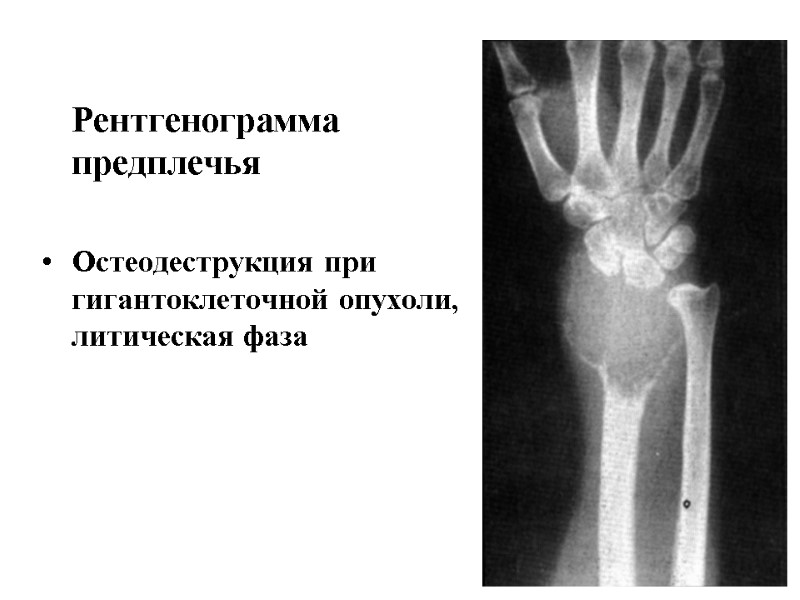

Рентгенограмма предплечья Остеодеструкция при гигантоклеточной опухоли, литическая фаза